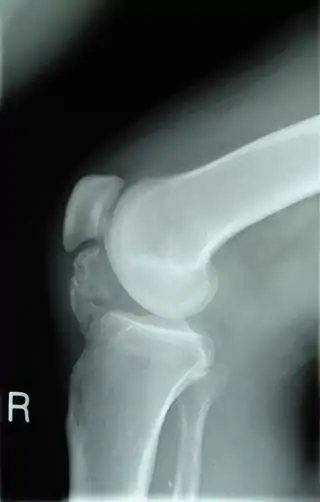

![]() Radiografía lateral de una rodilla que muestra la osificación de los tejidos peritendinosos en un paciente con osteocondroma. | ||

Los osteocondromas se diagnostican y se supervisan mediante el uso de radiología. Generalmente los tumores crecen hacia el exterior en las piernas o en los brazos, sin embargo, muy pocos casos crecen hacia el interior del hueso.